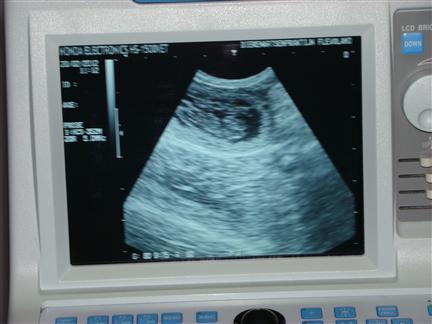

nog eens het zelfde pupje |

| Je kon het hartje ook al fanatiek zien kloppen |

op basis van de ontwikkeling van het hartje is de uitgerekende datum op 22 maart 2012 vastgesteld |